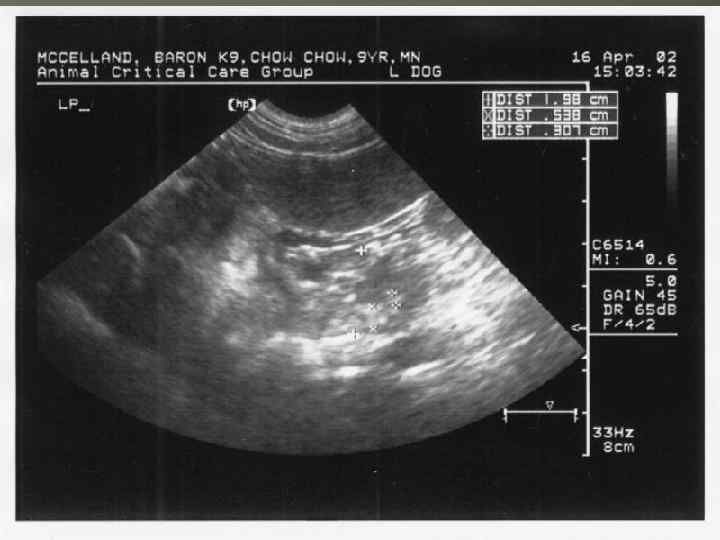

ИНСТРУМЕНТАЛЬНАЯ ДИАГНОСТИКА ОСТРОГО ПАНКРЕАТИТА УЗИ Лапароскопия Дуоденоскопия Рентгенография грудной клетки и брюшной полости КАФЕДРА ХИРУРГИИ МОСКОВСКОГО ФАКУЛЬТЕТА

ИНСТРУМЕНТАЛЬНАЯ ДИАГНОСТИКА ОСТРОГО ПАНКРЕАТИТА УЗИ Лапароскопия Дуоденоскопия Рентгенография грудной клетки и брюшной полости КАФЕДРА ХИРУРГИИ МОСКОВСКОГО ФАКУЛЬТЕТА

КАФЕДРА ХИРУРГИИ МОСКОВСКОГО ФАКУЛЬТЕТА

КАФЕДРА ХИРУРГИИ МОСКОВСКОГО ФАКУЛЬТЕТА

КАФЕДРА ХИРУРГИИ МОСКОВСКОГО ФАКУЛЬТЕТА

КАФЕДРА ХИРУРГИИ МОСКОВСКОГО ФАКУЛЬТЕТА

КАФЕДРА ХИРУРГИИ МОСКОВСКОГО ФАКУЛЬТЕТА

КАФЕДРА ХИРУРГИИ МОСКОВСКОГО ФАКУЛЬТЕТА